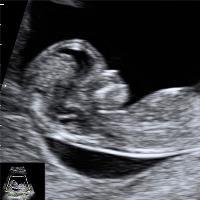

کمبود ویتامین دی در بارداری چه نشانه‌ها و عوارضی برای مادر و نوزاد دارد؟ چطور می‌توان فقر ویتامین D در دوران حاملگی را جبران کرد؟

عدم فقر و کمبود ویتامین دی در دوران بارداری اهمیت بسیار زیادی دارد. چرا که ویتامین D یکی از ویتامین‌های پر اهمیت بدن بوده  که D2  و D3 مهم‌ترین آنها هستند. تامین این ویتامین امروزه کار پیچیده‌ای نیست و نباید کمبود آن، مخصوصا در دوره بارداری، جهت پیشگیری از ایجاد اختلال در سیستم‌های بیولوژیکی مادر و نوزاد نادیده گرفته شود. کلینیک دکتر وهاب آقایی، در این مقاله قصد دارد در مورد تاثیرات ویتامین D در بدن، مخصوصا در دوران بارداری بپردازد.